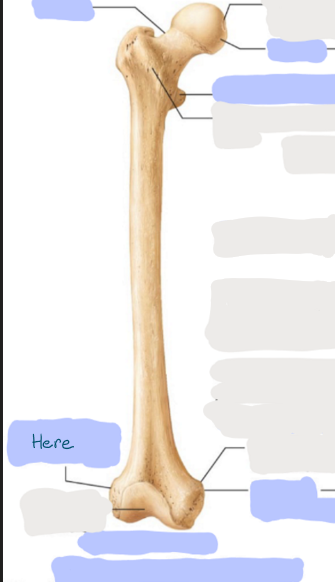

What is this picture of?

Posterior view of the Right Femur

What is here?

Where is the Head of the Femur?

What is here?

Where is the Lesser Trochanter of the Femur?

What is here?

Where is the Linea Aspera of the Femur?

What is here?

Where is the Medial Condyle of the Femur?

What is here?

Where is the Medial Epicondyle of the Femur?

What is here?

Where is the Greater Trochanter of the Femur?

What is here?

Where is the Lateral Condyle of the Femur?

What is here?

Where is the Lateral Epicondyle of the Femur?